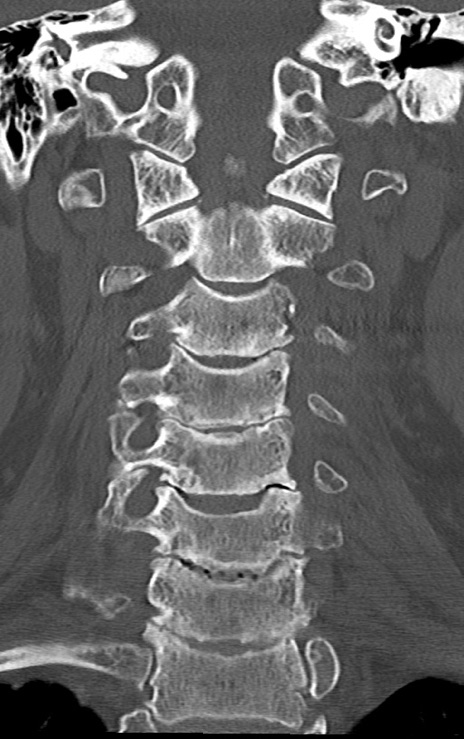

頚椎CT

矢状断像